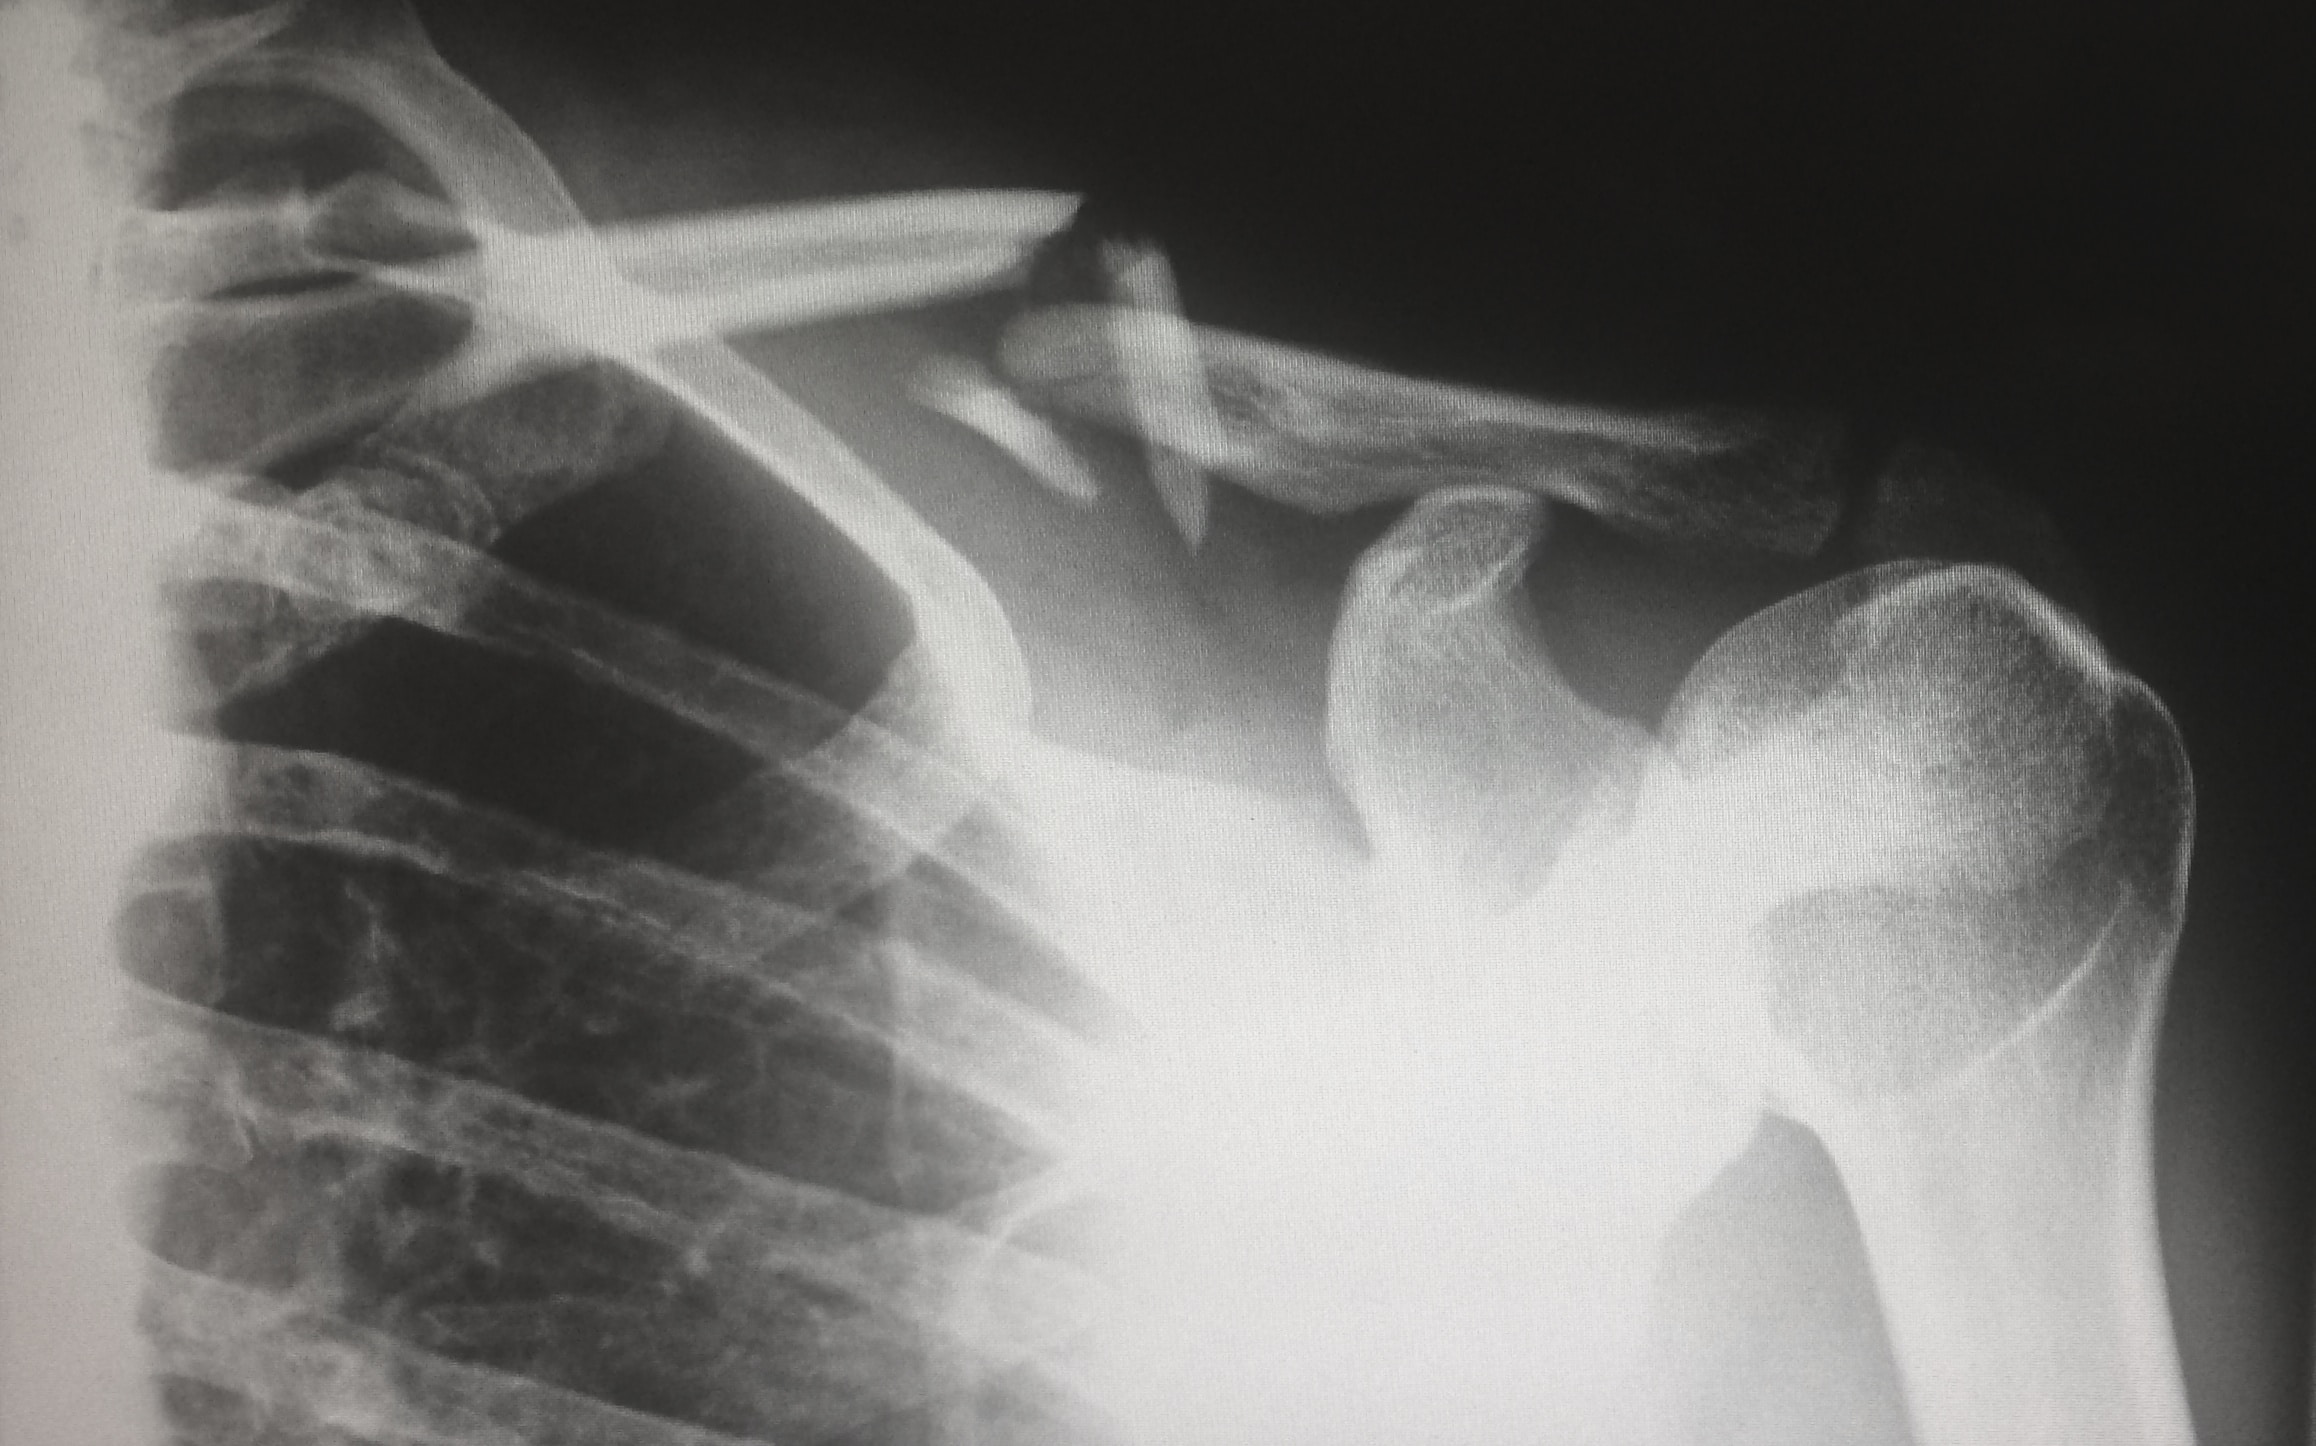

•An XRay of his pelvis was requested- see following image

Radiological diagnosis of Osteochondroma

- Benign neoplasms arising from small cartilage nodules within the periosteum

- More common in the extremities- Distal femur, proximal tibia and proximal humerus in descending order

- They are rare in the pelvis- approximately 5%. Osteochondroma of the pubic ramus is very rare.